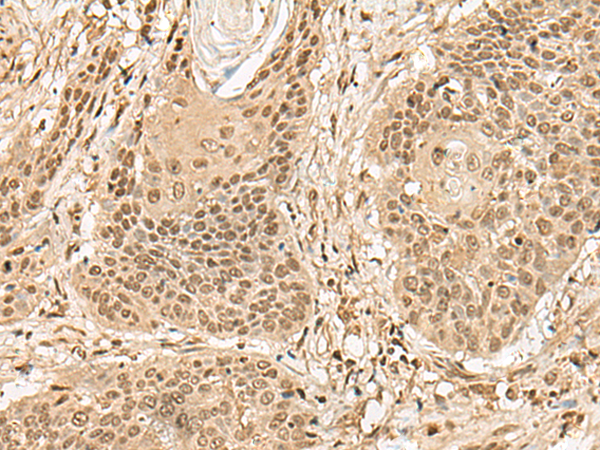

分类: 科研抗体货号: P13457别名: TAMALIN应用: IHC反应种属: Human, Mouse, Rat